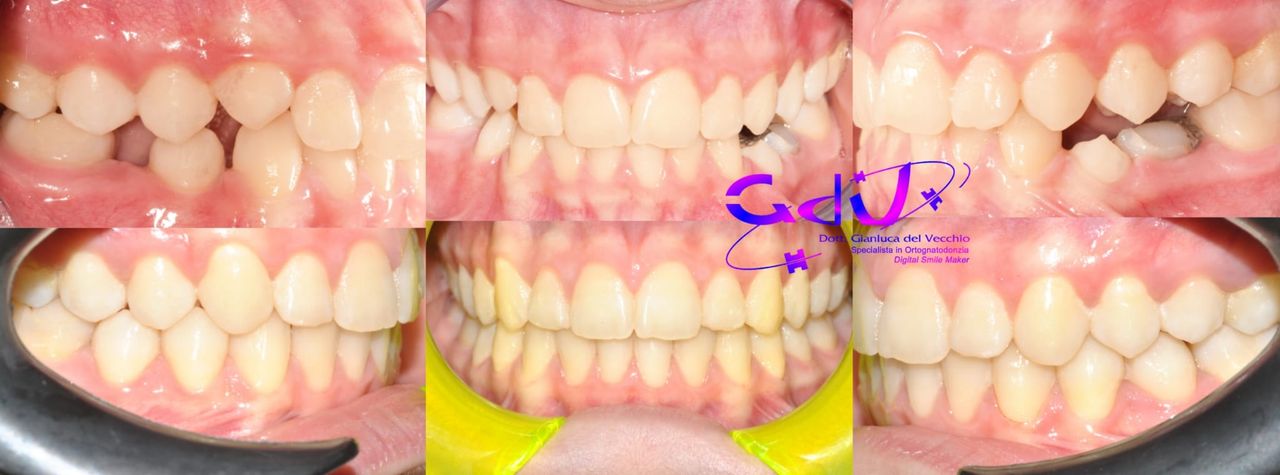

Il dottor Gianluca del Vecchio si occupa esclusivamente di ortognatodonzia, grazie anche alla collaborazione multidisciplinare di una équipe davvero entusiasmante e all’utilizzo di strumenti diagnostici e terapeutici all’avanguardia in ortognatodonzia. Particolare è la sua capacità di condurre i giovani pazienti ad affrontare, nella massima sicurezza emotiva e clinica, qualsiasi eventuale condizione di dolore derivante, ad esempio, da carie o da altre patologie, ma soprattutto di risolvere tutte quelle condizioni di “denti storti”, così spesso causa di disagio psicologico o di fenomeni deprecabili, quale il bullismo.

Queste le ragioni che consentono di trattare le malocclusioni, sia dei bambini che degli adulti, con protocolli scientificamente validati come i più veloci, affidabili e confortevoli.

Il dottore ha acquisito una concezione quanto più pratica e moderna della disciplina e utilizza apparecchietti di diversi colori di tipo mobile e fisso, ma anche terapie sia estetiche che invisibili, fiore all’occhiello di poche realtà in Italia. Per terapie estetiche e invisibili si intendono quelle in grado di spostare i denti, senza che traspaia nulla dalla bocca o con stelline e fili bianchi, esattamente come i denti del paziente.